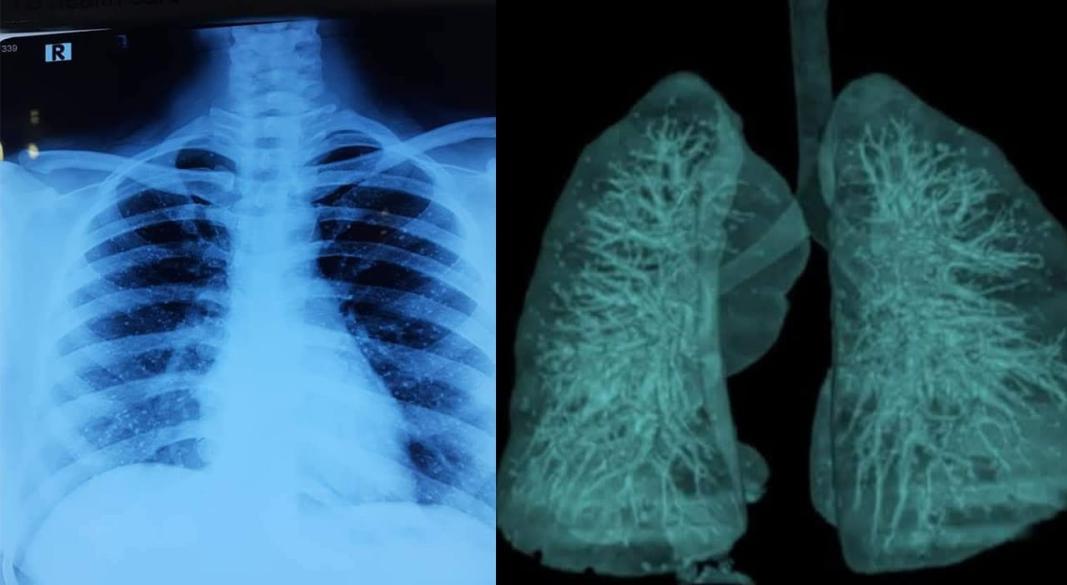

উপসর্গকে গুরুত্ব দিয়ে সতর্কতামূলকভাবে চিকিৎসক একটি চেস্ট এক্স-রে করার পরামর্শ দেন। পরীক্ষার ফলাফল হাতে আসার পর চিকিৎসকরাও বিস্মিত হন। রিপোর্টে দেখা যায়, তার ফুসফুসে অসংখ্য ক্ষুদ্র পাথরের মতো কণা জমে আছে।

চিকিৎসা বিজ্ঞানের ভাষায় এই বিরল রোগটির নাম পালমোনারি এলভিওলার মাইক্রোলিথিয়াসিস (Pulmonary Alveolar Microlithiasis), সংক্ষেপে পিএএম। এ রোগে ফুসফুসের অ্যালভিওলাইয়ের ভেতরে ক্যালসিয়াম ফসফেট জমে ক্ষুদ্র ক্ষুদ্র পাথরসদৃশ গঠন তৈরি হয়।

বিশ্বব্যাপী এ রোগের প্রাদুর্ভাব অত্যন্ত কম। প্রতি ১০ লাখ মানুষের মধ্যে গড়ে মাত্র একজন এ রোগে আক্রান্ত হন। এখন পর্যন্ত বিশ্বে নথিভুক্ত রোগীর সংখ্যা প্রায় দেড় হাজারের মতো।